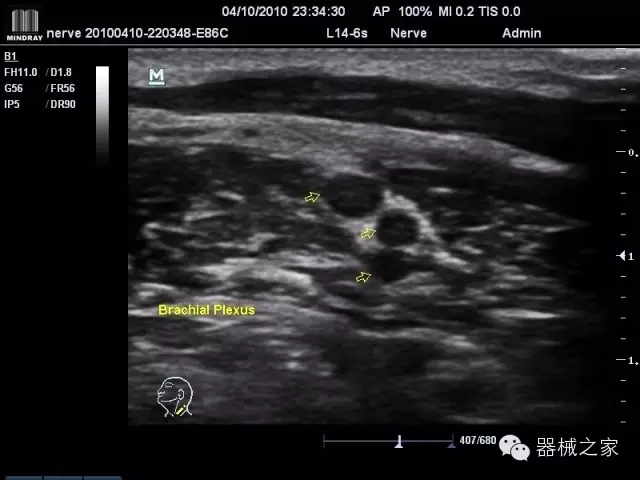

臨床圖片賞析

產(chǎn)品特點

·裝載有采用Multi-Core多核處理的非嵌入式平臺,成像效率大大提高,并且能夠給用戶帶來高速、多任務(wù)并行信號處理體驗;

·優(yōu)秀的圖像效果、強大的功能體驗、豐富的探頭選擇、合理的便攜式設(shè)計,全中文顯示及病人管理界面,使得M7在任何場合、任何時候都能快速響應(yīng)更好的心血管、腹部、婦產(chǎn)、小器官等常規(guī)超聲檢查以及肌骨、神經(jīng)、顱腦、術(shù)中等新興領(lǐng)域的使用需求;